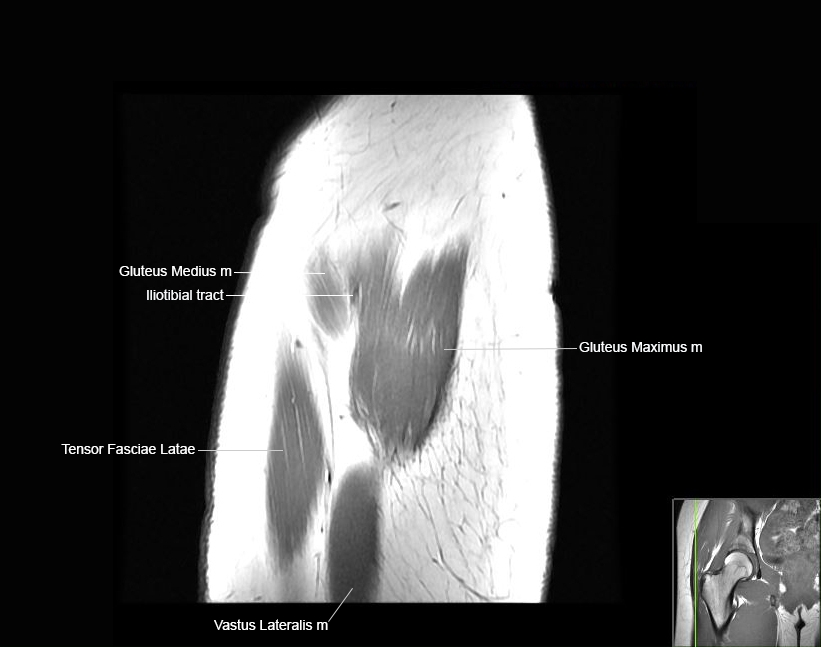

MRI Hip Anatomy

Scroll using the mouse wheel or the arrows